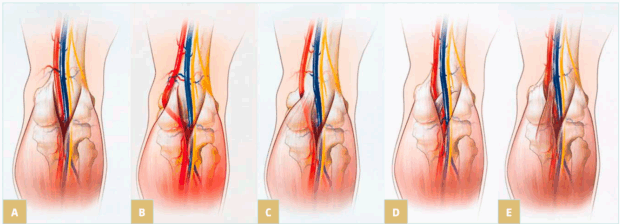

Different anatomical variations may be involved. A first condition is compression by an aberrant insertion of the lateral head of gastrocnemius; this is the most frequent situation, often associated with fibrous bands and/or fibrotic perivascular tissue; but also, a more lateral insertion of the medial head of gastrocnemius muscle to the femoral condyle can compress the vein. Another etiology is hypertrophy of the upper part in gastrocnemius and soleus muscles, with shortening of the sural triceps: type 6 in the Whelan and Rich classification.7 Obese people often present with this pattern. Figure 1 illustrates the anatomy of popliteal fossa and the classification of popliteal entrapment syndrome (into 4 types), showing common variants responsible for arterial entrapment8 A new classification into 6 types (by Levien) added type V where both popliteal artery and vein are compressed and type VI, functional entrapment: no visible anatomical anomaly, but symptoms appear during exercise due to muscle hypertrophy.9

Figure 1. Illustration of the anatomy of popliteal fossa and the classification of popliteal entrapment syndrome. Graphic illustrations show normal anatomy of popliteal fossa and common variants responsible for arterial entrapment. A) Normal popliteal artery is adjacent to and lateral to medial head of gastrocnemius muscle, which is normally attached just superior to medial femoral condyle. B) Type I. Popliteal artery takes abnormal course medial to normally attached medial head of

gastrocnemius muscle. C) Type II. Abnormal embryologic development results in medial head of gastrocnemius attached more laterally than is normal. D) Type III. Popliteal artery and gastrocnemius are normally positioned, but fibrous band is responsible for entrapment. E) Type IV. Popliteal artery courses beneath popliteus muscle. Reproduced from reference 8: Bradshaw et al. Cardiovasc Diagn Ther. 2021;11(5):1159-1167. doi:10.21037/cdt-20-186. Copyright 2021,

Cardiovascular Diagnosis and Therapy. Material under Creative Commons License CC BY-NC-ND 4.0. [The figure in reference 8 is an adaptation from Macedo TA, Johnson CM, Hallett JW, et al. Popliteal artery entrapment syndrome: role of imaging in the diagnosis. Am J Roentgenol.

2003;181:1259-1265 by permission from the Mayo Foundation for Medical Education and Research, all rights reserved.]